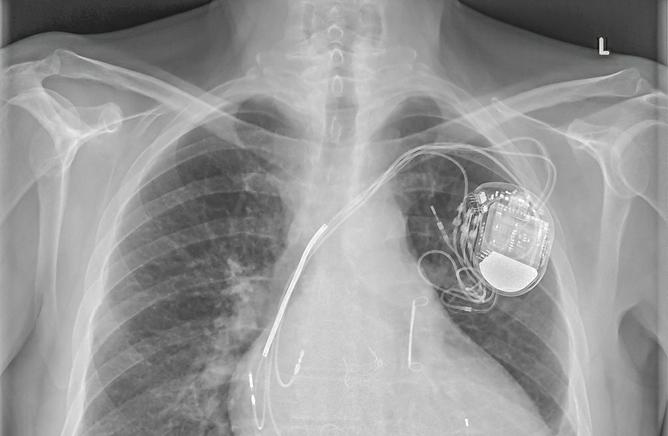

Le pace-maker n’est plus un frein aux examens IRM. Une nouvelle étude prospective a été réalisée pour évaluer l'innocuité de l'IRM avec un champ magnétique de 1,5 Tesla chez 1509 patients porteurs d'un pacemaker ou d'un défibrillateur implantable (42%).

Dans l'ensemble, les patients ont subi 2103 examens IRM thoraciques et non thoraciques, considérés comme cliniquement nécessaires. Elle est publiée dans le NEJM.

Le mode de stimulation a été changé en mode asynchrone pour les patients dépendants de la stimulation. L’évaluation comprenait les effets indésirables et les changements dans les variables qui indiquent la fonction du plomb, du générateur et l'interaction avec le tissu environnant.

Pas de complication majeure

Aucun événement indésirable cliniquement significatif à court ou à long terme n'a été signalé.

Dans neuf examens IRM, le stimulateur du patient a été réinitialisé en mode de secours. Dans un cas seulement, un stimulateur cardiaque mis en place depuis moins d'un mois, l’appareil s'est réinitialisé et n'a pas pu être reprogrammé. Il a été remplacé par la suite. Le changement notable le plus fréquent des paramètres de l'appareil était une diminution de l'amplitude de l'onde P, qui est survenue chez 1% des patients.

A long terme, les changements notables étaient une diminution de l'amplitude des ondes P et une augmentation du seuil de capture auriculaire.

Dans l’ensemble, les tests sont plus que rassurants.